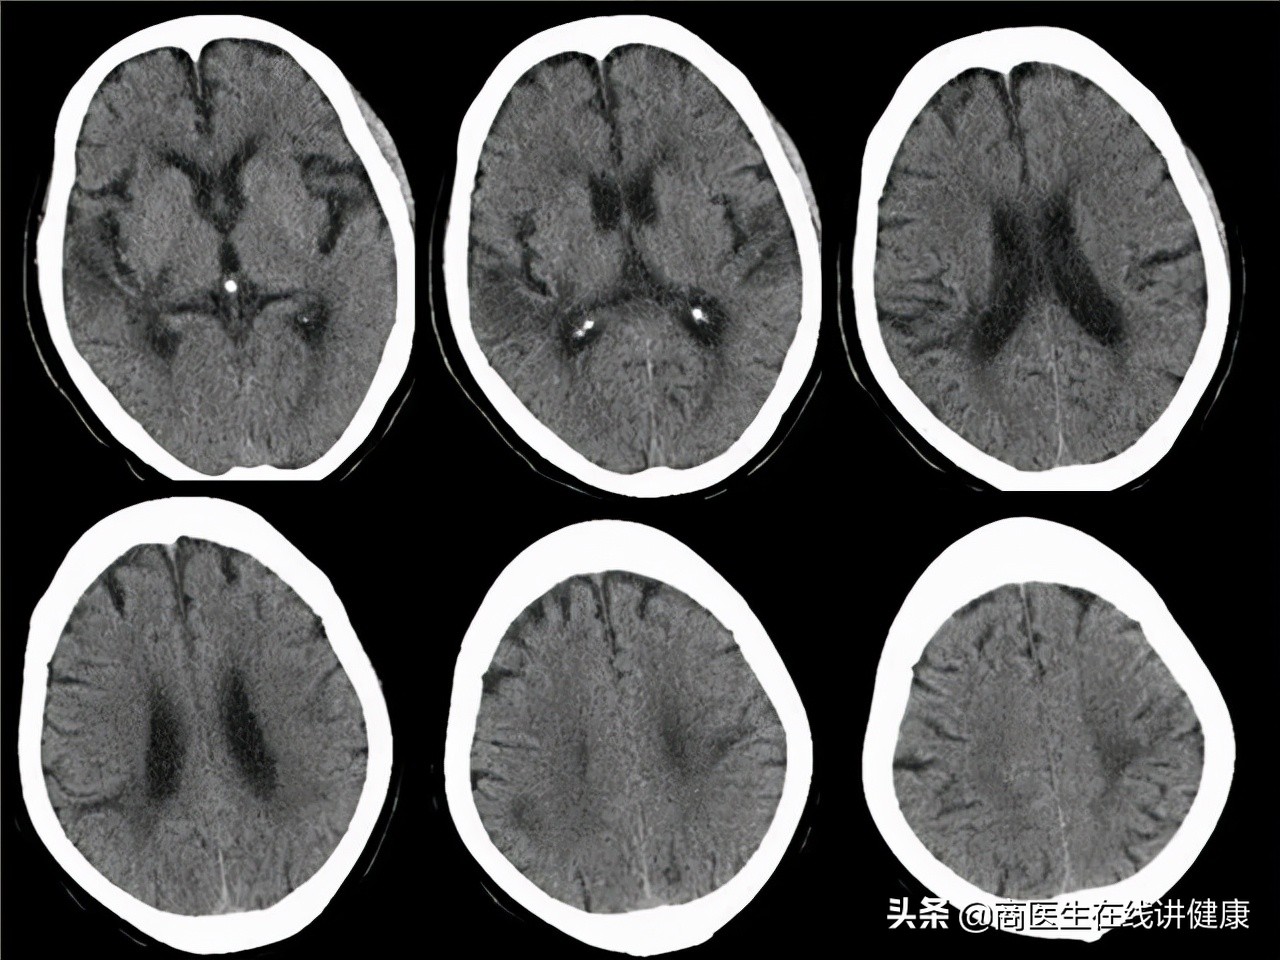

通过头部CT和MRI发现患者头部没有出现病变,但是存在髓鞘受损的情况。